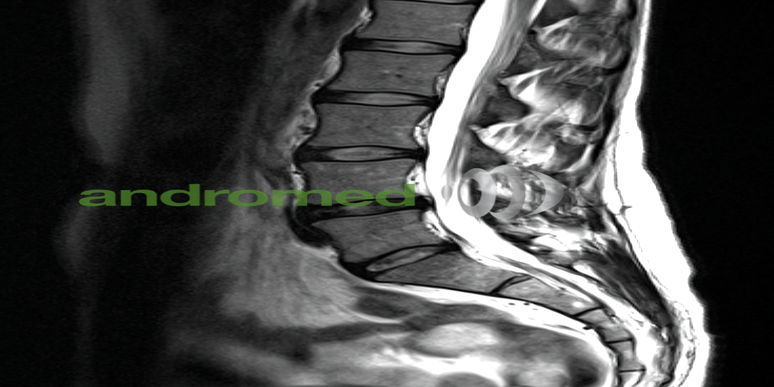

Diagnose im Bild: MRT-Diashow

2. Orthopädie: In der Orthopädie ist die MRT eine unverzichtbare Methode zur Untersuchung von Gelenkschäden, Bandscheibenproblemen und Sehnenverletzungen. Zudem sollten bei der erstmaligen Verwendung technischer Begriffe Abkürzungen erklärt werden. Dank der hohen Auflösung der MRT-Bilder kann eine genaue Lokalisierung und Charakterisierung von Verletzungen erreicht werden, was eine erleichterte Entscheidungsfindung bezüglich der Behandlung ermöglicht.